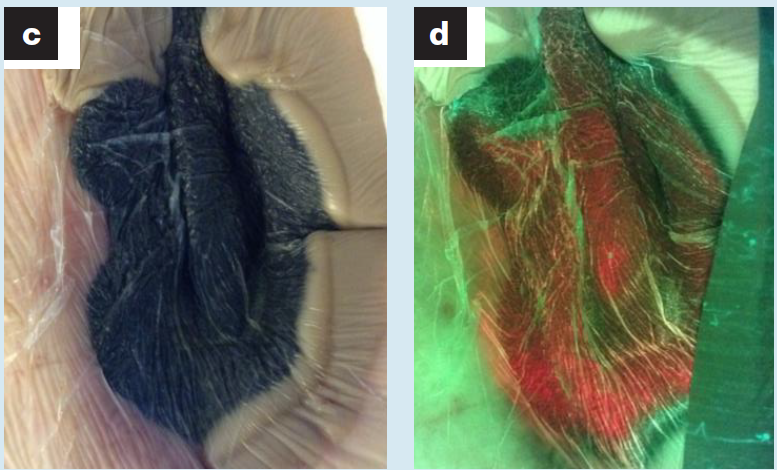

Bacterial fluorescence imaging as a predictor of skin graft integration in burn wounds

Hanson-Viana, E. et al. Burns 2024

The use of the MolecuLight i:X in managing burns: a pilot study

Blumenthal, E et al. J Burn Care Research 2018

Utility of MolecuLight i:X for managing bacterial burden in pediatric burns

Farhan, N et al. J Burn Care Research 2020

Imaging of bacteria in burn wounds treated with split thickness grafts in MEEK/MESH technique: a pilot study with first experiences in clinical wound evaluation with autofluorescence

Alawi, SA et al. HMPC 2019 (Article in German)

Assessing Pediatric Burn Wound Infection Using a Point-of-Care Fluorescence Imaging Device

Turner, E et al. J Burn Care Res 2024

Diagnosing burn wounds infection: The practice gap & advances with MolecuLight bacterial imaging

Farhan, N. et al. Diagnostics 2021